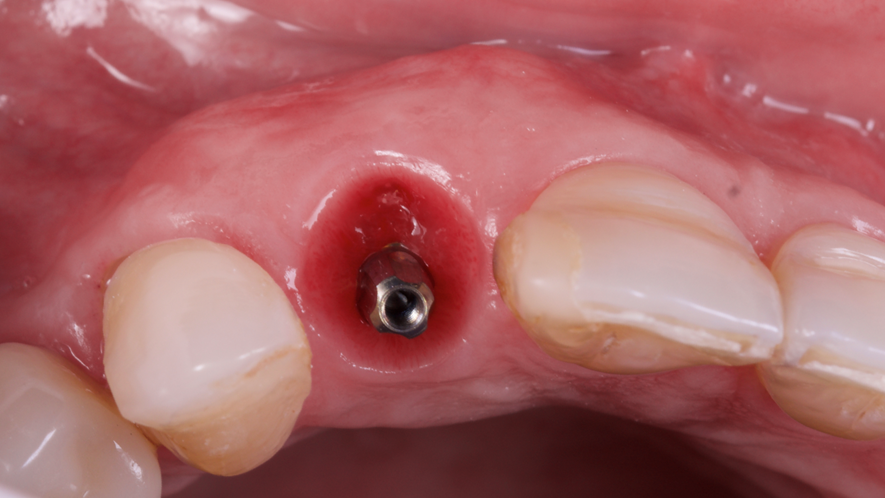

Este trabalho tem como objetivo relatar um caso clínico de exodontia minimamente invasiva de um incisivo lateral superior com fratura radicular, realizando implante imediato em alvéolo pós-extração, enxerto de tecido conjuntivo subepitelial e osso bovino liofilizado para preenchimento de GAP, prontamente à instalação de pilar reto e provisório imediato.